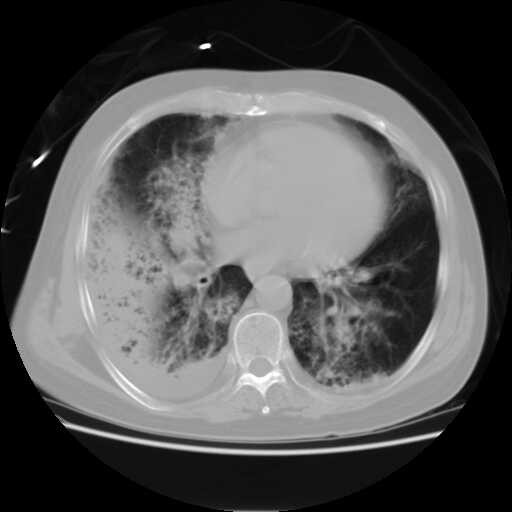

患者,男,60岁,病史如下:

2008.8.17ct

病变从8.11-8.17明显改变,增多,以蜂窝状改变为主,类蜂窝肺,似弥漫性肺泡癌,但是病变进展太快,不符合弥漫性细支气管肺泡癌。因此考虑为特殊微生物感染,多以霉菌类常见,建议细菌微生物学检查。

疑点二:影象表现怪异,大片阴影内见多发筛孔征,如何解释.

间质为主,血管炎性水肿?

结合临床慢支炎肺气肿,肺心病病史,三次胸片观察可见病情发展变化迅速,病情凶险,考虑多重感染伴ards.